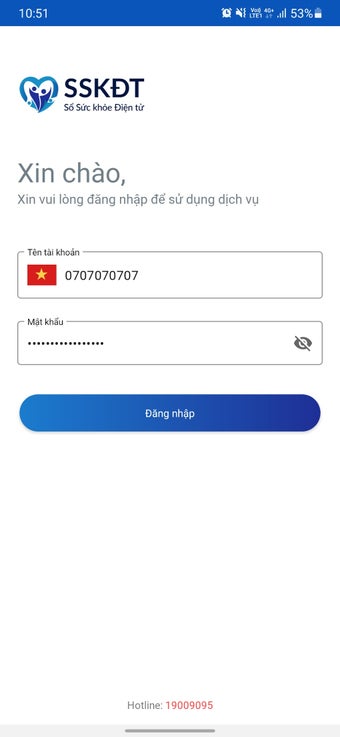

สำหรับความช่วยเหลือในการติดตั้งหรือใช้งานแอปพลิเคชัน บันทึกข้อมูลสุขภาพอิเล็กทรอนิกส์สำหรับแพทย์ โปรดติดต่อฮอตไลน์ที่ทีมพัฒนา ทีมงานกำลังทำงานอย่างหนักเพื่อปรับปรุงแอปพลิเคชันและให้บริการในการสู้รบกับ COVID-19 สำหรับประเทศและประชาชน